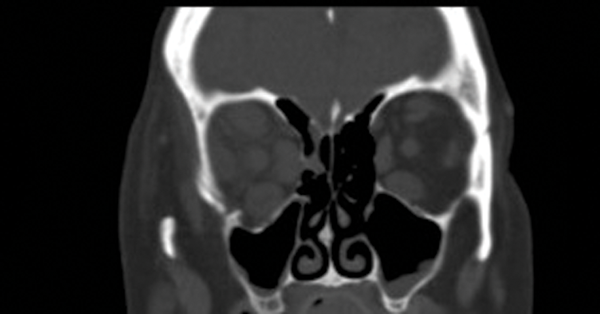

Figure 1.

Figure 2: Two CT coronal images showing an interruption in the floor of her right orbit.

Note the enlarged extraocular muscles in thyroid eye disease.